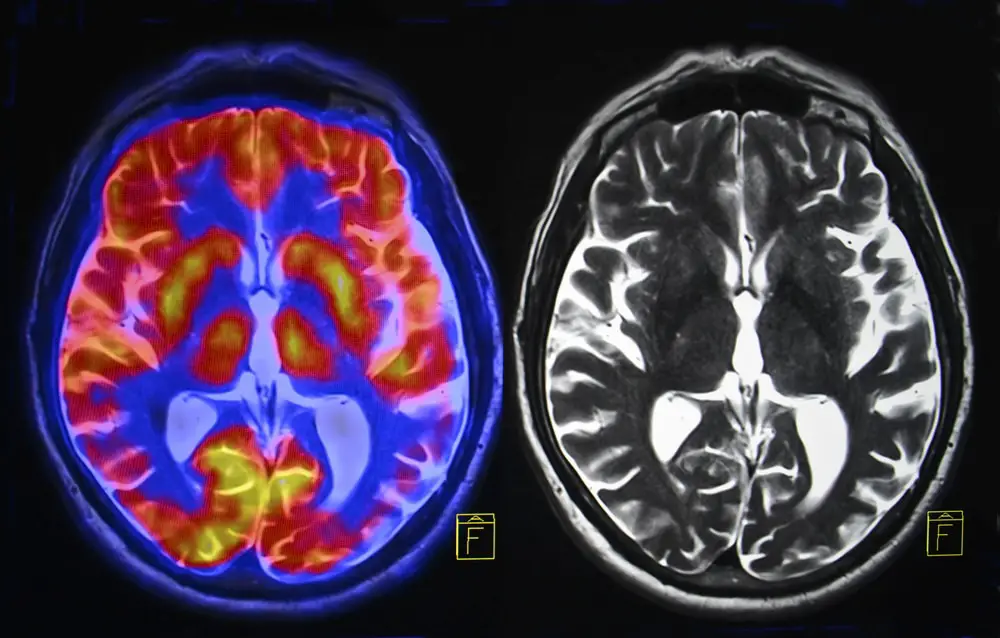

Brain cells lost to Alzheimer’s and Parkinson’s disease might soon be replaceable. Japanese researchers created enhanced vitamin K compounds that regenerate neurons three times better than natural vitamin K. Unlike current medications that only mask symptoms, these new compounds actually trigger the brain to grow fresh neurons. Scientists at Shibaura Institute of Technology combined vitamin K with retinoic acid to create molecules that cross into the brain and activate regeneration. Early tests in mice showed the compounds penetrate the blood-brain barrier and convert to active forms that stimulate neuron growth. Neurodegenerative diseases rob millions of people of their memories, movement, and independence each year. Current treatments offer no cure and provide limited relief.

Medications available today for Alzheimer’s, Parkinson’s, and Huntington’s disease ease symptoms but cannot stop or reverse brain damage. As neurons die, patients lose memory, cognition, and motor control. Quality of life declines until round-the-clock care becomes necessary. Families watch their loved ones fade while spending enormous amounts on caregiving and medical expenses.